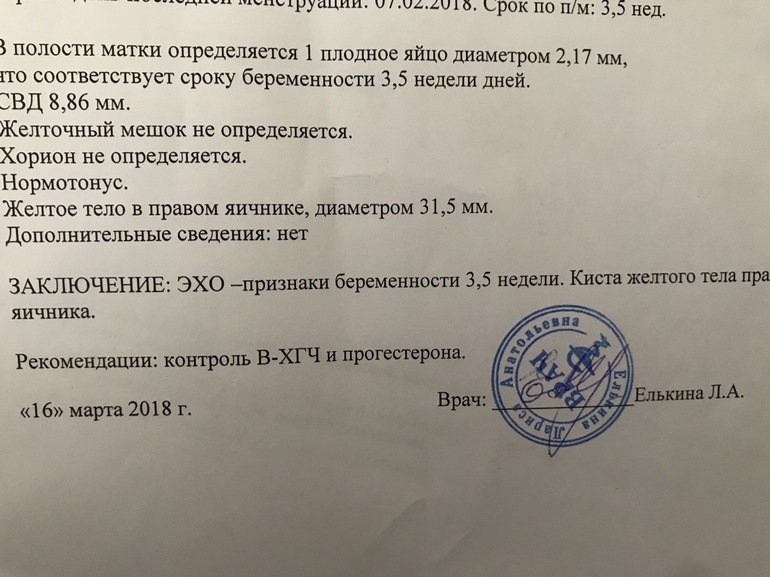

УЗИ двухплодной беременности на 5 неделе: Подборка изображений

Раздел: Калейдоскоп образов